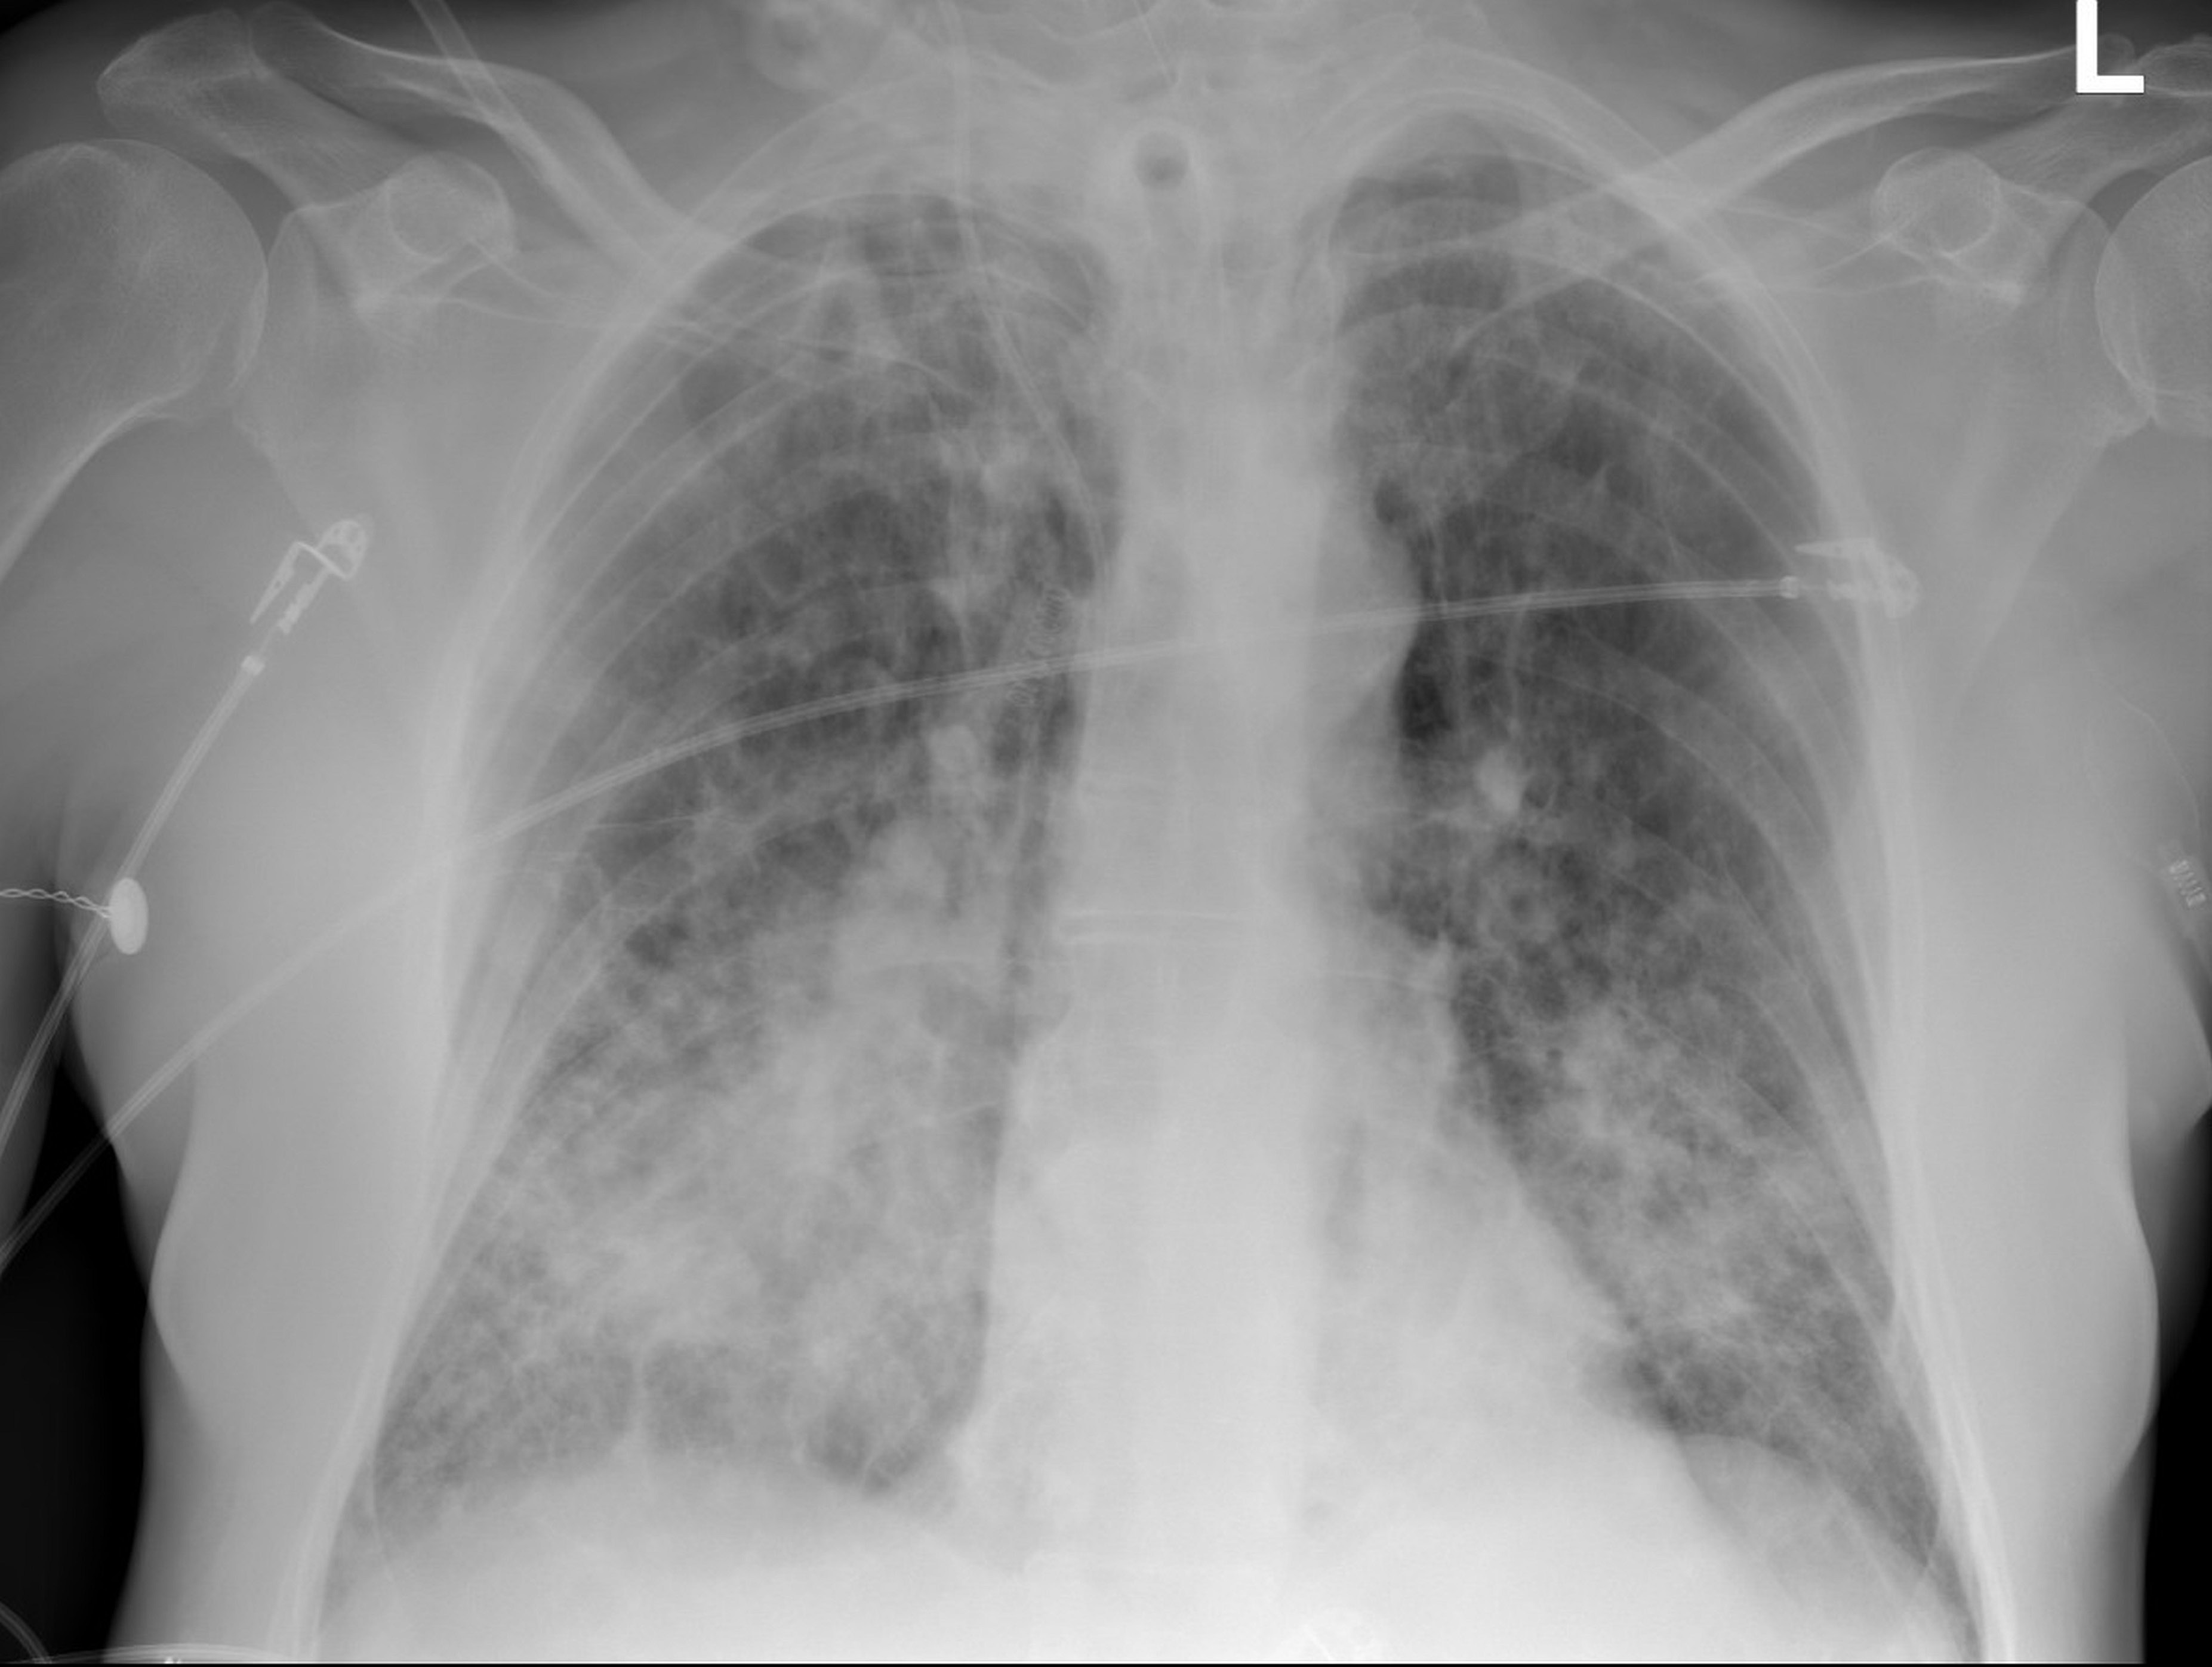

Chest radiography (chest X-ray – CXR) is less sensitive than chest CT. However, due to the limited availability and high costs of CT, CXR is performed first. Furthermore, in some countries, CXR cannot be followed up by CT, especially during a pandemic. For this reason, it is essential to describe the radiographic features which can be seen on a chest radiograph, not only by a radiologist, but also other specialists.4 Chest radiography in early and mild cases of COVID-19 may not reveal any pathologies. Studies from China showed that only 54.2% of non-severe disease cases presented with abnormalities on chest radiographs; in severe cases, almost 77% of patients had an abnormal chest radiograph.5 The most common radiographic features are patchy or diffuse asymmetric air-space opacities, consolidations, and ground-glass opacities (GGOs).6 The distribution of these features is frequently bilateral. The peripheral and lower zone distribution are the prevalent locations of these signs (Figure 1). Pleural effusion is a rare complication experienced by approx. 3% of patients. In these cases, there is no pathognomonic appearance of COVID-19 in the chest radiograph and the image is similar to other pneumonias.4 Due to this fact, CXR is not recommended for screening or use as a diagnostic tool for COVID-19. It should be noted that portable imaging equipment limits the transportation of patients and minimizes the risk of spreading the disease.7 Reports from radiology departments, including the University of Washington and Australian hospitals, highlighted a technique whereby an X-ray can be performed through a glass window and the patient does not leave the isolation room.8, 9